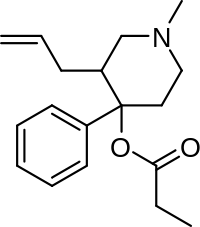

4-Phenylpiperidines

Pethidines (meperidines)

Structures

Prodines

Structures

Others

Structures